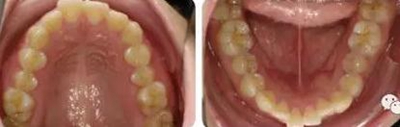

女性,24歲,主訴牙列不齊,面型突。

開唇露齒,閉口時唇肌緊張,反笑線,突面型。

上下牙列輕度擁擠,牙弓偏尖圓形;前牙深覆合深覆蓋;雙側(cè)磨牙尖牙偏遠(yuǎn)中關(guān)系。